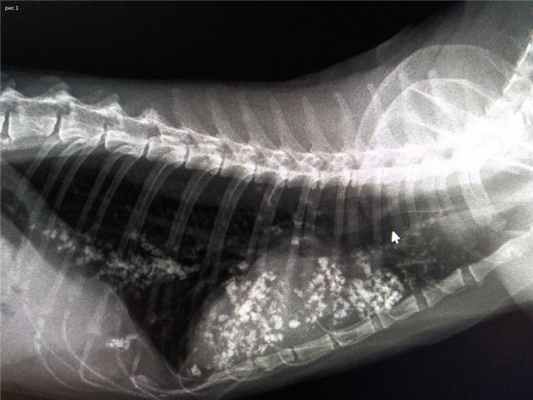

По данным анамнеза и осмотра животного было принято решение провести рентгенологическое обследование грудной полости.

По Rtg (рис 1,2) выявлено множество рентгеноплотных/контрастных очагов в грудной полости. Размер и форма тени сердца была не изменена

После общения с владельцами выяснилось, что накануне до начала кашля кот отказывался от корма, после принудительного кормления у него сразу была рвота. Симптомы продолжались 3 дня, а на 4-ые сутки владельцы обратились в стороннюю клинику, где диагностировали инородное тело кишечника. Провели лапаротомию и удалили пуговицу из кишки.

После операции через рото-пищеводный зонд дали сульфат бария с целью контрастирования кишечника и выявления сохранения возможной непроходимости. Провели два рентгеновских снимка с интервалом в 6 часов, по результатам которых не было выявлено наличие непроходимости желудочно-кишечного тракта.

Пациенту был поставлен окончательный диагноз - аспирационная пневмония.